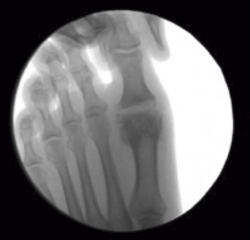

Se debe acceder a la articulación mediante 1 o 2 portales articulares situados a ambos extremos de la articulación a nivel dorsal (Figura 1). Deben ser unos portales un poco más grandes de lo normal, de 2 a 3 mm, que nos permitan un buen acceso a la articulación y poder extraer los fragmentos de cartílago que no podamos triturar. La fresa a utilizar es la Shannon® larga o Shannon® 44, que permite acceder a toda la articulación (Figura 2). En ocasiones, podemos utilizar la fresa de tipo pino (llamada así por su forma).

Figura 1. Portal articular a través del cual la fresa Shannon® elimina el cartílago y prepara las superficies articulares.

Figura 2. Cruentación de las superficies articulares con la fresa Shannon® bajo control radiológico.